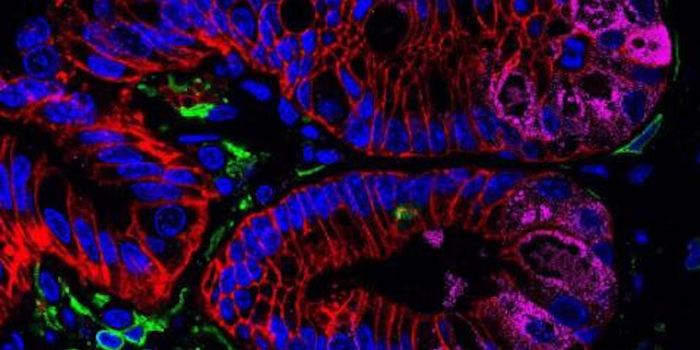

OCT 10, 2021Cell & Molecular BiologyThere is a well-known causal connection between smoking and lung cancer, and most research on lung cancer has been focus ...

OCT 19, 2020CancerCancer is a disease characterized by DNA mutations. These mutations, while sometimes small, can cause havoc in a cell&rs ...